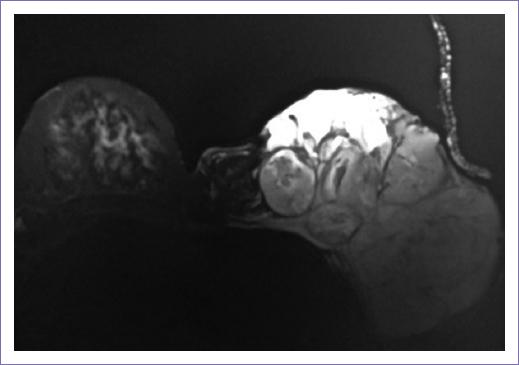

Recibió radioterapia adyuvante 50 Gy/25 fracciones, con técnica 3D conformal con campos tangenciales y axilosupraclavicular (Fig. 2); la toxicidad desarrollada durante el tratamiento fue radiodermitis grado I. Durante el seguimiento, siete meses después se documentó mediante tomografía con emisión de positrones dos nódulos pulmonares con hipermetabolismo, maximum standardized uptake value (SUVmax) 3.7 y 2.8, así como trombos en la vena pulmonar izquierda, arterias ilíacas comunes y externas. Un mes después, la paciente empezó con cefalea holocraneana con intensidad del dolor en escala visual analógica 8/10, por lo que se documentó con estudios de imagen una lesión intraaxial frontal izquierda de 50 x 42 mm, de características metastásicas (Fig. 3), motivo por lo que se consideró candidata a tratamiento quirúrgico, seguido de irradiación a holocráneo 30 Gy/10 fracciones (Fig. 4). Durante el último tratamiento presentó dificultad respiratoria súbita y se documentó tromboembolia pulmonar bilateral metastásica, motivo de fallecimiento (Fig. 5).

Al inicio de la presentación, el tamaño del tumor varía entre 0.5 y 40 cm3. El sarcoma del estroma mamario crece por invasión directa y su diseminación es hematógena, principalmente a pulmón, pleura, hígado (con menor frecuencia), médula ósea y cerebro. El involucro ganglionar axilar es muy raro, se presenta en menos del 5% de los pacientes y usualmente se presenta en etapas avanzadas9. En el caso reportado, la paciente presentó invasión local y hematógena cerebral y pulmonar.